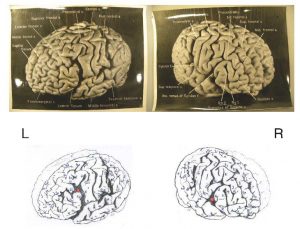

نتایج اولیه تحقیقات روی مغز این فیزیکدان برجسته چندان جالب از آب در نیامد، چون مغز اینشتین حتی از متوسط ابعاد انسانهای دیگر هم کوچکتر بود و بر اثر افزایش سن دچار زوال شده بود. اما بعدتر در سال ۱۹۸۵ معلوم شد در دو بخش مغز او نسبت سلولهای غیر عصبی به ازای هر نورون ( سلول عصبی ) به طرز عجیبی بیشتر از بقیه افراد است. هاروی در سال ۱۹۹۰ کشف کرد قسمت بالایی وسط نیمکره مغز اینشتین که لوب یا لخته آهیانه نامیده می شود، فاقد یک ساختار شیار مانند رایج در مغز انسانهای دیگر است. محققان می گویند احتمالا این فقدان باعث شده اتصالات عصبی که وظیفه درک فضایی و محاسبات را بر عهده دارند، بیشتر شوند.

به تازگی دین فالک، انسان شناس دانشگاه ایالتی اوهایو و همکارانش ۱۲ عدد از عکسهای هاروی را از موزه ملی سلامت در ایالا متحده قرض گرفته و آنها را با تصاویر مشابه از ۸۵ نمونه مغز دیگر مقایسه کرده اند. در این تحقیق ساختارهایی مشخص شدند که در تحقیقهای قبلی نادیده مانده بود. مثلا توسعه بیش از حد قشر حسی نیمکره راست مغز احتمالا باعث شده بود اینشتین ویولن نواز خوبی از آب در بیاید. پیچیدگی ها و الگوهای چین ها در نقاط خاصی از مغز اینشتین مثل قشر جلویی پیشانی، لوب آهیانه و قشر بینایی متفاوت است. ساختار چین ها در قشر پیشانی که برای تفکر انتزاعی از جنس افکاری شبیه نظریه نسبیت کافی در اختیار مغز به کار می رود، بسیار پیچیده است و احتمالا این پیچیدگی فضا و ساختار عصبی کافی در اختیار مغز او قرار داده تا بتواند به طرز غیر متعارفی فکر کند.